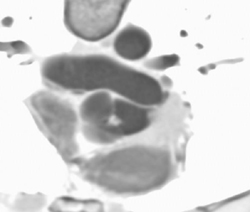

Right Aortic Arch With Chd